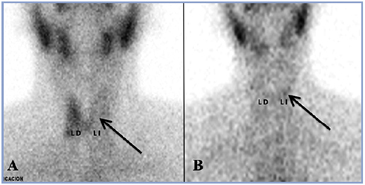

La paciente estaba hipertiroidea y el cintigrama tiroideo mostró ausencia de captación del lóbulo izquierdo (Figura 1). La VHS fue 29 mm/h, tiroglobulina sérica 113 ng/mL (VN: 2,7-21 ng/mL) y los anticuerpos anti-tiroglobulina, anti-tiroperoxidasa y anti-receptor de TSH fueron negativos. Después de un mes de permanecer hipertiroidea y con febrículas diarias, inició aumento de volumen y dolor en el lóbulo tiroideo derecho asociado a gran compromiso del estado general. Un nuevo cintigrama mostró ausencia total de captación en la región tiroidea. Se inició tratamiento con prednisona 0,5 mg/kg/día el que se mantuvo por 3 semanas desapareciendo rápidamente el dolor, la fiebre y el compromiso del estado general. A los 4 meses de iniciados los síntomas estos habían desaparecido y la función tiroidea se había normalizado.

La paciente evolucionó clínicamente con una tiroiditis subaguda migratoria ya que inicialmente consultó por dolor cervical lateralizado a izquierda coincidente con la ausencia de captación del lóbulo tiroideo izquierdo en el cintigrama y un mes después se agregó dolor y aumento de volumen del lóbulo derecho con un nuevo cintigrama que mostró ausencia total de captación en la región tiroidea. Esto probablemente explicaría el larvado y prolongado cuadro clínico que presentó la paciente. Si bien la tiroiditis subaguda debuta con dolor unilateral hasta en un 45% de los casos13, no se encontró descrito en la literatura este patrón cintigráfico. Lo interesante del caso es la asimétrica distribución inicial del radiofármaco, con preservación de la captación de un lóbulo concomitante con la TSH frenada, lo que sumado a la VHS poco elevada, obligó a descartar otras causas de hipertiroidismo.